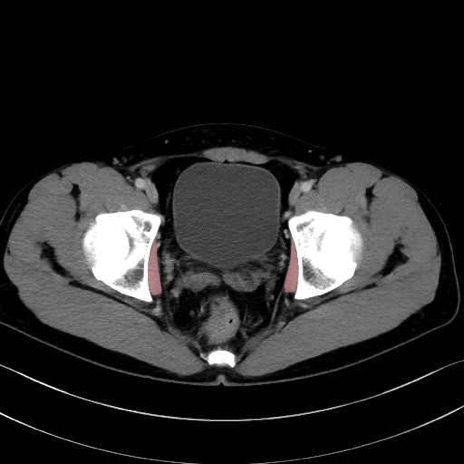

内閉鎖筋 (Obturator internus)